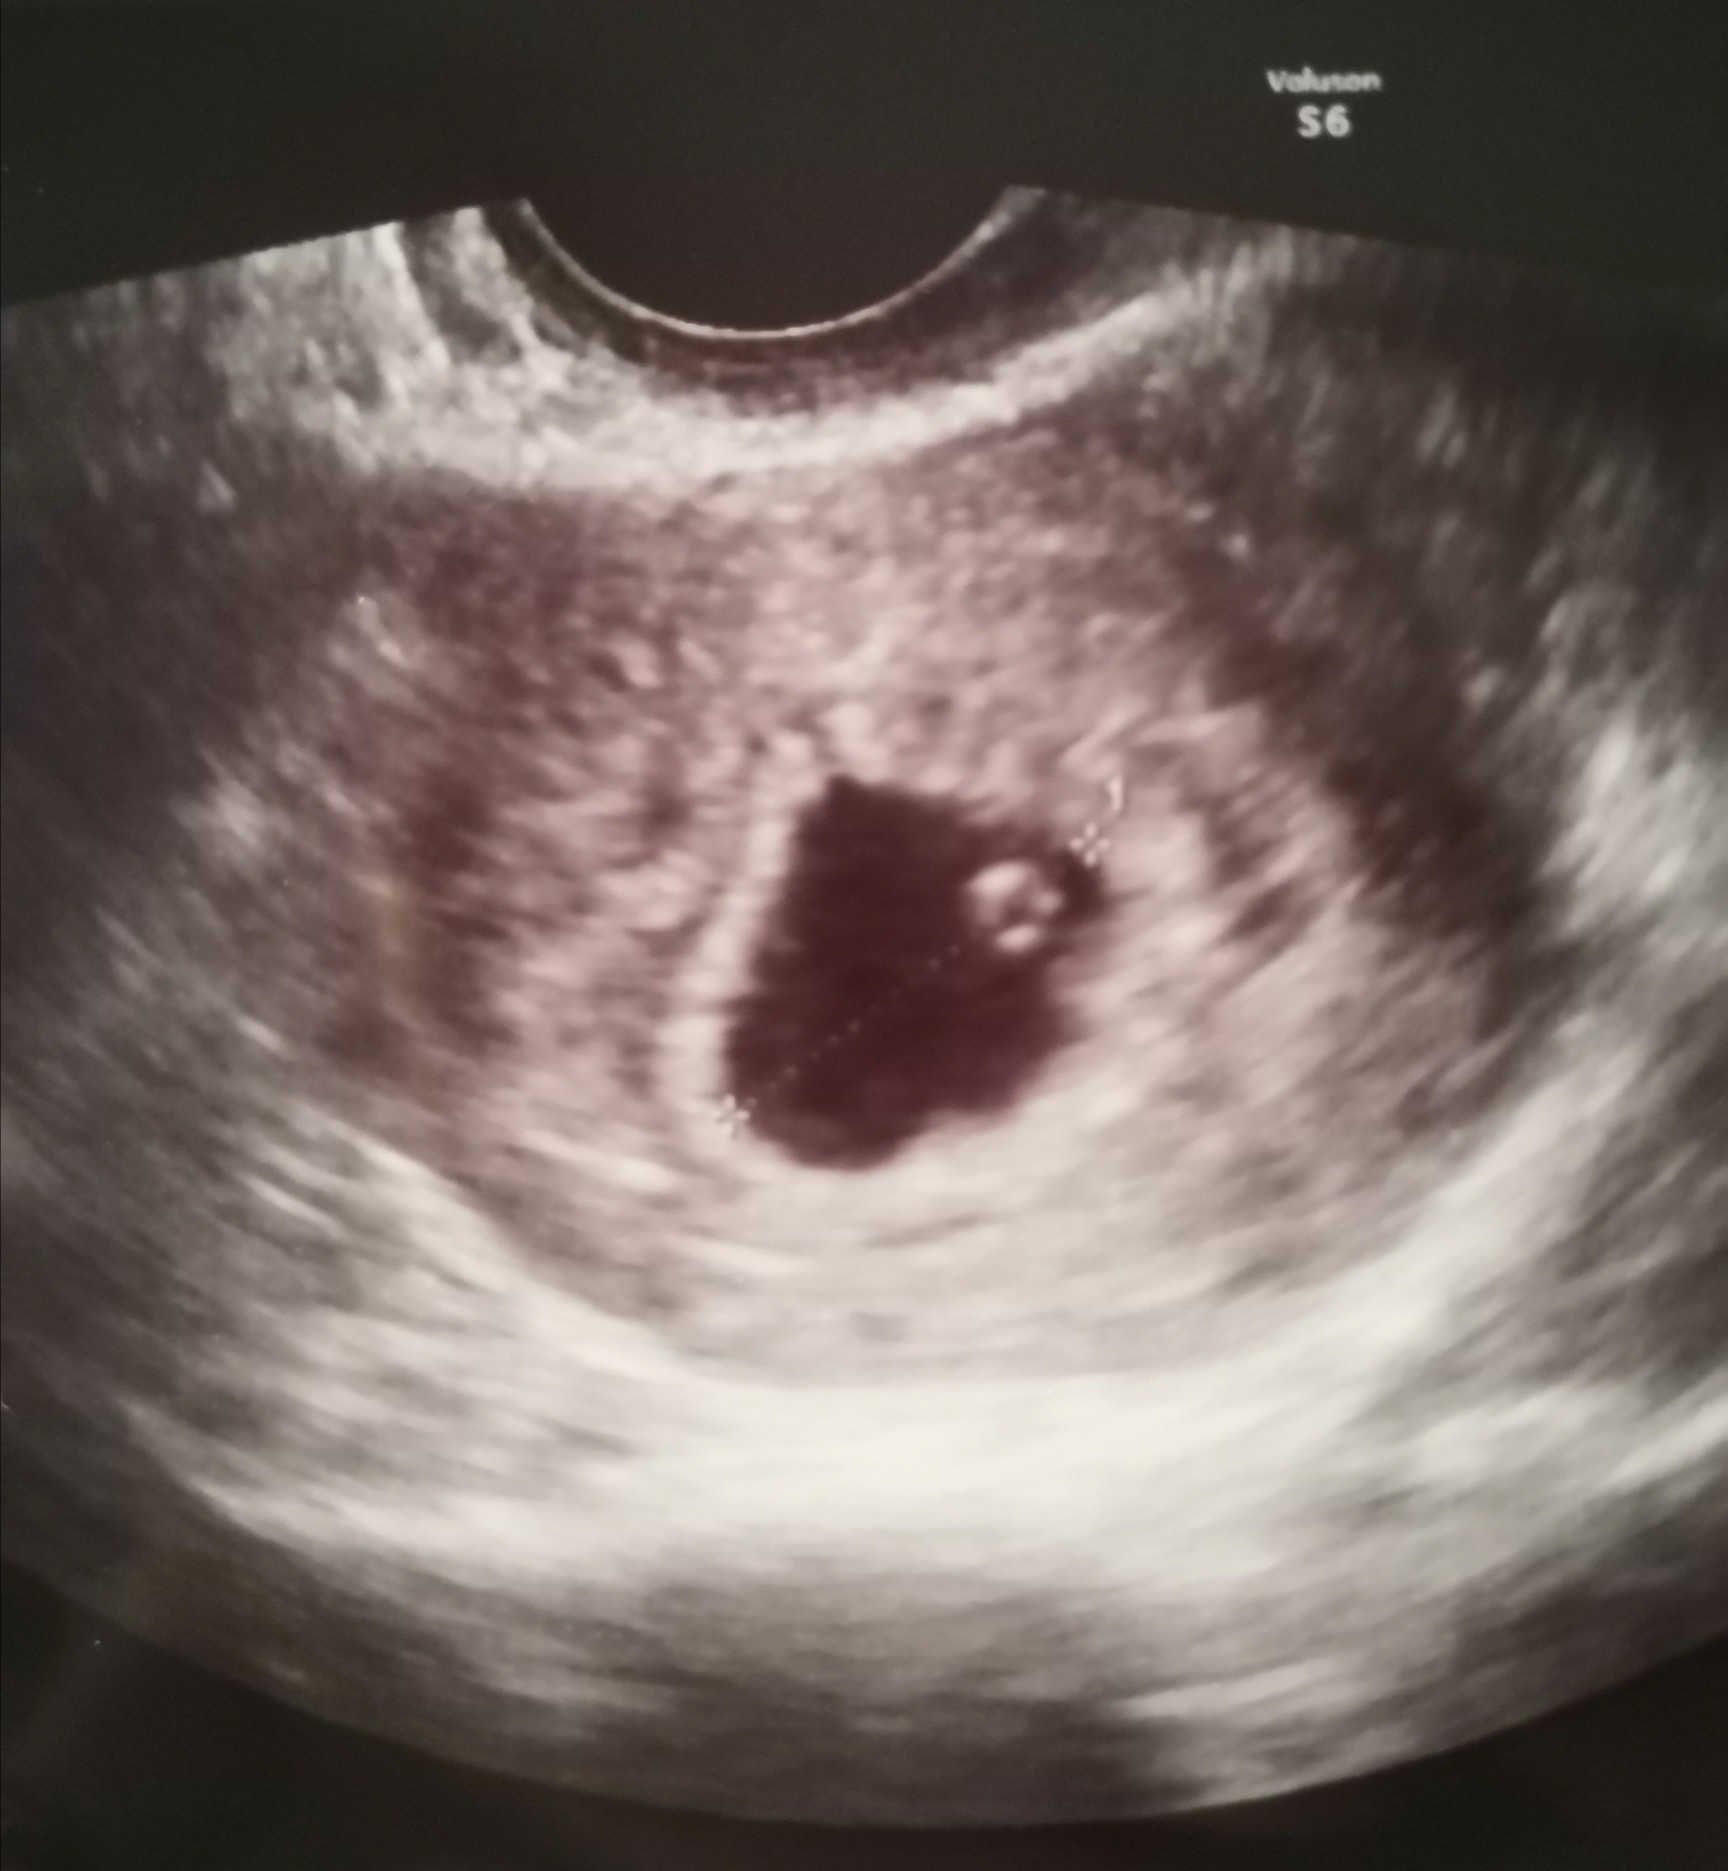

Bardzo mi przykroZobacz załącznik 1289962

Tak bardzo mi przykroZobacz załącznik 1289962

Nie ma już nadziei? Może się jeszcze pojawi zarodek…Nie zmienia to faktu że zarodka brak

A ten punkcik w pęcherzyku to co?Porównałam usg u mojego lekarza. Miałam pęcherzyk 13.8 to było w poniedziałek. U tego lekarza 19 mm a wiek ciąży oszacował ten pierwszy na 5+5 co się praktycznie zgadzało z datą ostatniej miesiaczki a ten teraz też oszacował na 5+5 przy 19 a tak naprawdę przyrosło idealnie 4 mm czyli 1 mm na dzień.